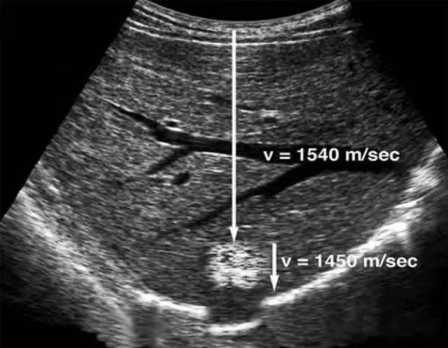

声速失真伪像是由于实际声速差别过大引起,超声表现为图像失真,测量误差。在人体中,声波在不同组织中传播速度差异较大。在超声诊断中,肺及胃肠道气体中的平均声速约为350m/s,骨骼中的平均声速约为3850m/s,而超声仪将声速设定为1540m/s ,并在此基础上计算反射界面的距离。

超声波实际传播过程中的速度会高于或低于1540m/s,当经过的组织超声波传播速度高于1540m/s,所需时间缩短,最后结果是,仪器判断的位置会比实际位置更靠近探头;反之,当经过的组织超声波传播速度低于1540m/s,仪器判断的位置会比实际位置远一些。

肝右后叶一个富含脂肪成分的高回声结节,可见该结节远方的横膈线样强回声连续性“中断”。

声波在穿越该富含脂肪的结节时声速实际只有1450 m/s,慢于其在软组织中传播速度的平均值1540m/s,也就是说声波在穿越该结节时所花费的时间更长,致使其后方横膈的回波时间也延长了。导致声像图表现横膈连续性“中断”。